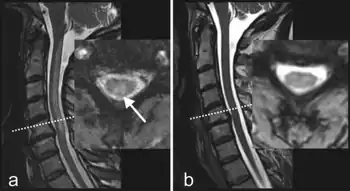

MRI-T2 images may reveal increased signal within the white matter of the spinal cord, predominantly in the posterior columns and possibly in the spinothalamic tracts.